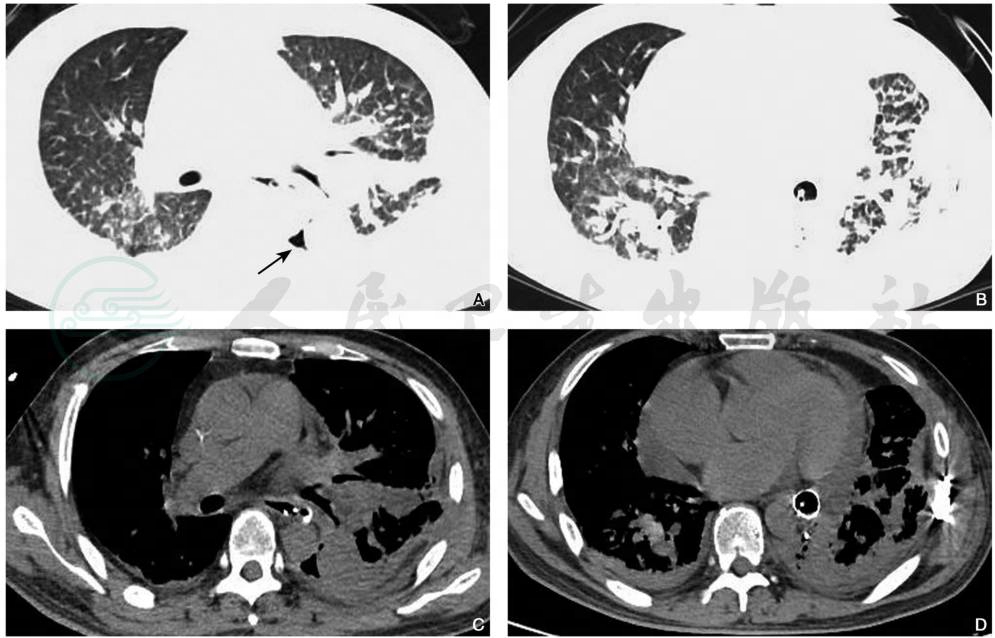

图2肺裂伤

男性,38岁,胸部CT平扫肺窗(A、B)显示双肺野内见多发斑片状高密度影,左肺下叶为著。左侧胸腔内见局限性无肺纹理透亮区(箭)。同层纵隔窗(C、D)显示双侧胸腔积液,双侧胸膜增厚及心包积液。注:环形致密影为支架管

引自:中华影像医学·呼吸系统卷.第3版.ISBN:978-7-117-28903-0.主编:

(A)示双下肺膨胀不全,左侧气胸;治疗后1周复查(B)示双下肺实变影,左侧少许气胸。为治疗后2周复查

(C)示右下肺胸膜下残留少许斑片状及条索状高密度影